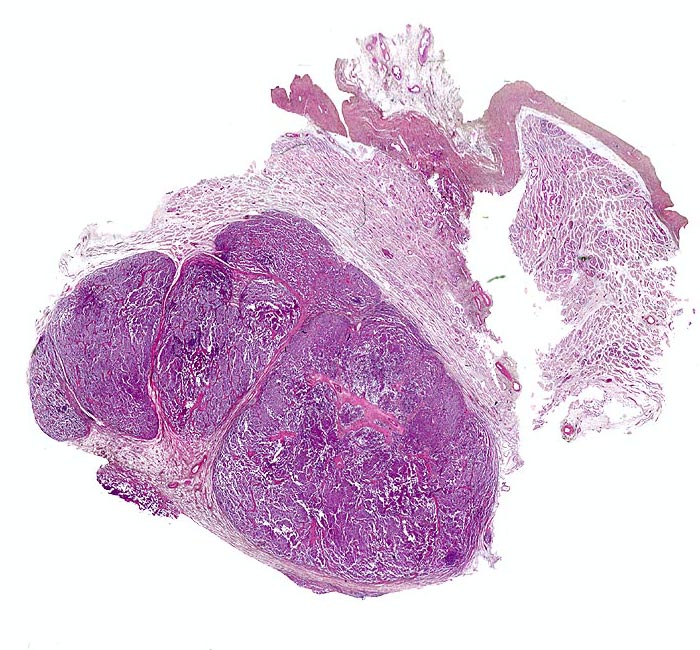

Makroskopisch imponieren Seminome als gut begrenzte weiche crèmefarbene Knoten oder diffuses Intiltrat. Mikroskopisch findet sich eine uniforme Population grosser Zellen mit prominentem zentralem Nukleolus, welche durch schmale Bindegewebssepten voneinander getrennte Nester bilden. Ein leukozytäres Entzündungsinfiltrat, synzytiotrophoblastäre Riesenzellen und Mikroverkalkungen können zusätzlich vorhanden sein. Gelegentlich induziert der Tumor eine ausgeprägte granulomatöse Entzündung. Dies kann zur Fehldiganose einer granulomatösen Orchitis führen.

• Scharf begrenzter Tumorknoten mit eosinophilen Nekrosearealen.

• Tubuläre Atrophie des angrenzenden Hodenparenchyms. Einige Hodentubuli enthalten stark atypische pleomorphe Keimzellen (Keimzellneoplasie in situ).